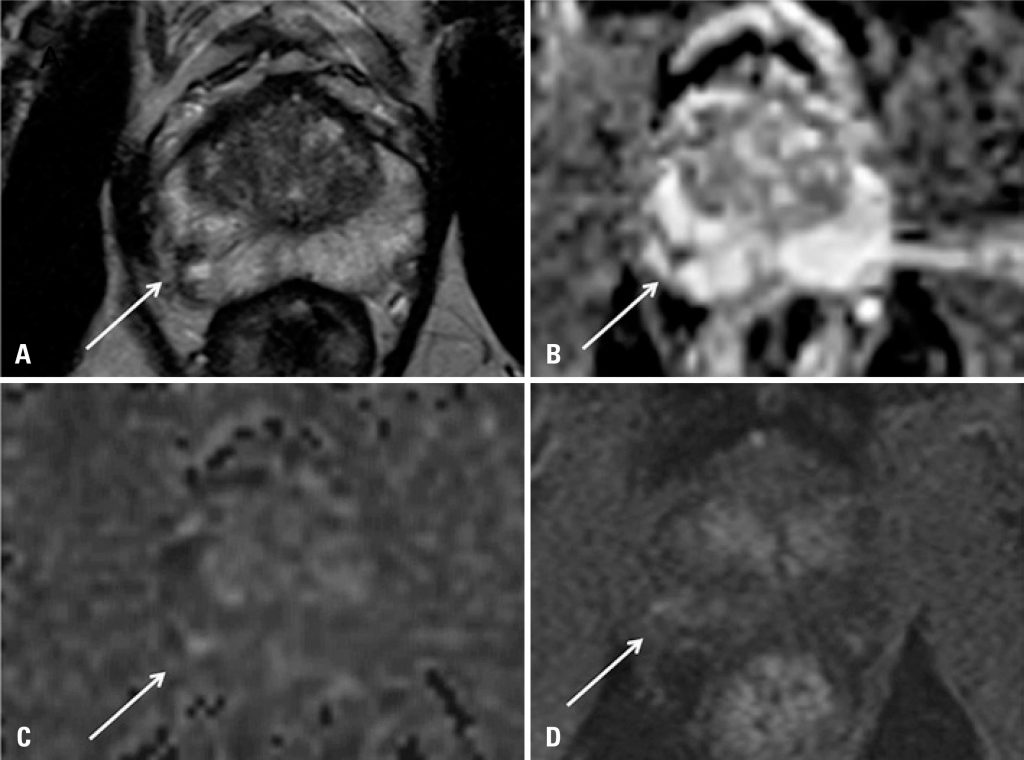

Figure 1

Contrast axial magnetic resonance imaging of the prostate

(A) T2-weighted; (B) apparent diffusion coefficient (ADC) map; (C) diffusion sequence and (D) perfusion sequence, showing a small nodule suspected to be a clinically significant malignancy in the periphery of the right lobe (arrows).